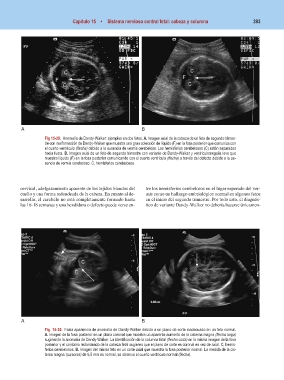

Fig 15-29. Anomalía de Dandy-Walker: ejemplos en dos fetos. A. Imagen axial de la cabeza de un feto de segundo trimes-

tre con malformación de Dandy-Walker que muestra una gran colección de líquido (F) en la fosa posterior que comunica con

el cuarto ventrículo (flecha) debido a la ausencia de vermis cerebeloso. Los hemisferios cerebelosos (C) están separados

hacia fuera. B. Imagen axial de un feto de segundo trimestre con variante de Dandy-Walker y ventriculomegalia leve que

muestra líquido (F) en la fosa posterior comunicando con el cuarto ventrículo (flecha) a través del defecto debido a la au-

sencia de vermis cerebeloso. C, hemisferios cerebelosos.

Fig. 15-30. Falsa apariencia de anomalía de Dandy-Walker debido a un plano de corte inadecuado en un feto normal.

A. Imagen de la fosa posterior en un plano coronal que muestra un aparente aumento de la cisterna magna (flecha larga)

sugiriendo la anomalía de Dandy-Walker. La identificación de la columna fetal (flecha corta) en la misma imagen de la fosa

posterior y el contorno redondeado de la cabeza fetal sugieren que el plano de corte es coronal en vez de axial. C, hemis-

ferios cerebelosos. B. Imagen del mismo feto en un corte axial que muestra la fosa posterior normal. La medida de la cis-

terna magna (cursores) de 6,5 mm es normal, se observa el cuarto ventrículo normal (flecha).